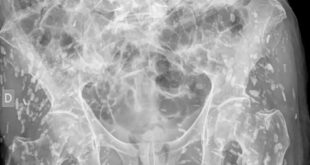

طبيب ينشر صورة صادمة لرجل تغزو جسده الديدان الشريطية

أبوظبي. ماي مول شارك أحد أطباء الطوارئ مؤخراً «واحدة من أكثر صور الأشعة السينية جنوناً التي شاهدها على الإطلاق»، إذ تُظهر الجزء السفلي من جسم شخص مصاب بمئات من بيوض الدودة الشريطية المتكلسة. وتعد الديدان الشريطية طفيليات تلتصق عادةً بداخل أمعاء مضيفها، وتمتص العناصر الغذائية مباشرة من الأمعاء، لكن قِلة …